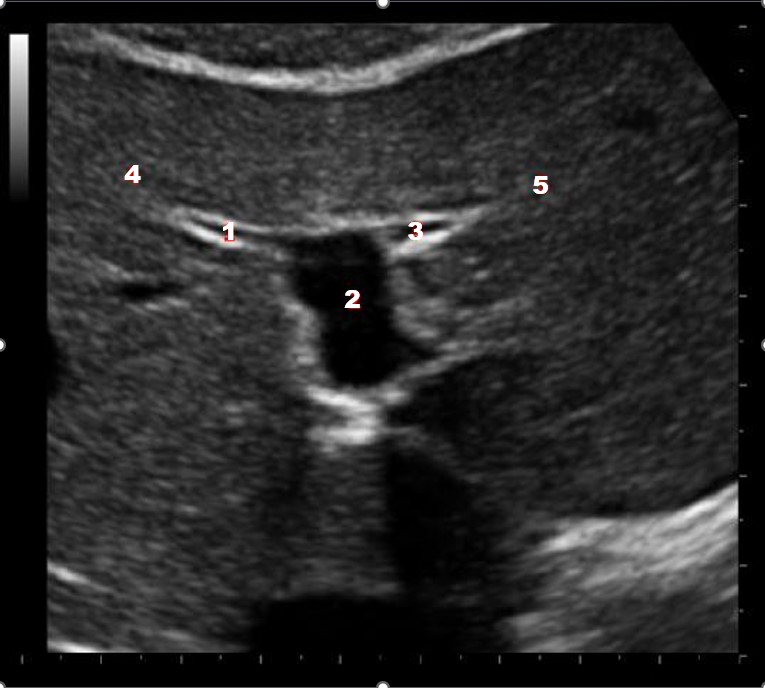

Which of the following structures is labeled number #1?

Left hepatic vein

What structure/vessel is indicated by #3?

Gastroduodenal artery

What structure/vessel is indicated by #2?

Head of pancreas

Which of the following structures is labeled #2?

Middle hepatic vein

What structure/vessel is indicated by #1?

Medial branch of LPV

Left portal vein

Which of the following structures is labeled #3?

IVC

Which of the following structures is labeled #6?

Medial left lobe

What structures last vessel is indicated by #4?

Which of the following structures is labeled #4?

Right hepatic vein

Which structure/vessel is indicated by #5?

Lateral left lobe